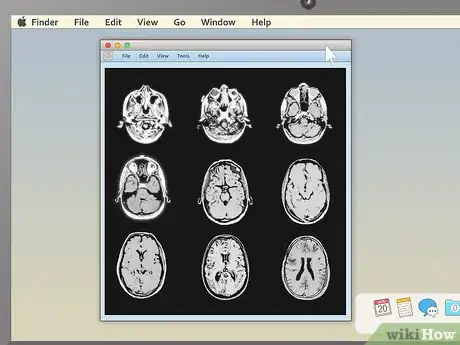

3Pick an appealing series layout. MRI programs almost always have the ability to display more than one image at once. This makes it convenient for doctors to compare different views of the same area or even MRIs taken at different times. For most non-doctors, it's easiest to simply choose a one-image-at-a-time layout and cycle through the images individually. However, there should be onscreen instructions to show two, four, or many more images at once, so feel free to play around with this feature.

3Use cross-sectional views to spot abnormalities in brain MRIs. MRIs of the brain tissue are often used to check for brain tumors, abscesses, and other serious problems that can affect the brain. The easiest way to see these things is usually to choose the cross-sectional view, then descend slowly from the top of the head downward. You're looking for anything that's not symmetrical — a dark or light patch that's on one side but not the other is cause for concern.

- Brain tumors often take the form of round, golf ball-like growths in the brain which will usually show up as either bright white or dull grey surrounded by a ring of white. However, other brain problems (like multiple scleroses) can also have a whitish appearance, so this alone may not be a sign of a brain tumor.